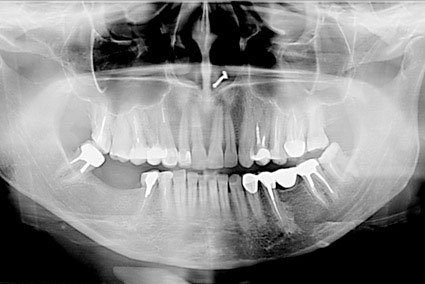

Ортопантомограф - це стоматологічний рентген

апарат для отримання панорамних зображень щелепної зони і суглобів щелепи. Його

головне достоїнство полягає в тому, що знімок ортопантомографа показує

одночасно обидві щелепи і всі зуби. У цьому його принципова відмінність від

прицільної рентгенівської зйомки.

Найбільш повну інформацію несуть панорамні

знімки. Для отримання панорамного знімка випромінювач (рентген-трубка) і

приймач (рентген-плівка або цифровий напівпровідниковий датчик) рухаються

навколо голови пацієнта по певній траєкторії.